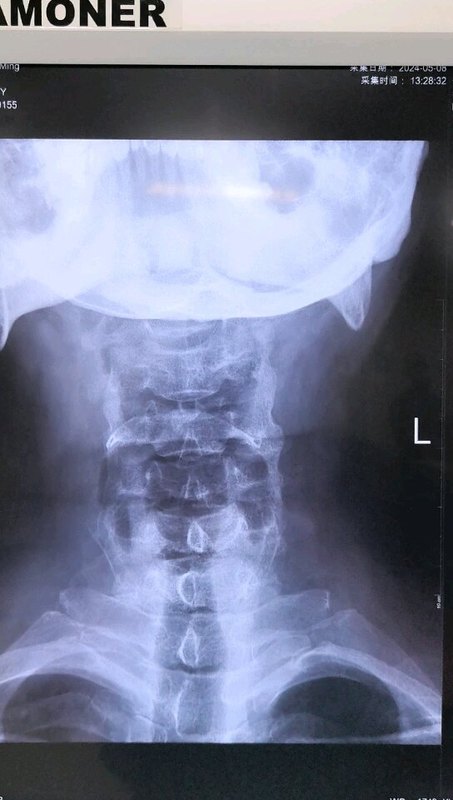

不少患者查出頸椎病后,發(fā)現(xiàn)不是頸椎受壓就是脊髓受壓,這兩種情況有什么不同呢?哪一種更嚴(yán)重呢?如果既壓迫到神經(jīng),又壓迫到脊髓,又該怎么辦呢?頸椎病壓到神經(jīng)和脊髓,有什么不同?事實上,這個問題是在對比神經(jīng)根型頸椎病和脊髓型頸椎病。頸椎病由于頸椎退化等各種原因?qū)е轮車纳窠?jīng)根、脊髓、血管等組織受壓,導(dǎo)致出現(xiàn)一系列癥狀。根據(jù)受壓組織不同,頸椎病又分為許多類型,其中最常見的就是神經(jīng)根型頸椎病,最嚴(yán)重的就是脊髓型頸椎病。顧名思義,神經(jīng)根型頸椎病常由于頸椎間盤突出等原因?qū)е律窠?jīng)根受壓,患者常會出現(xiàn)上肢的放射性疼痛、麻木、無力等癥狀;而脊髓型頸椎病壓迫到脊髓,患者除了上肢癥狀外,還會出現(xiàn)下肢的走路踩棉花感、走路不穩(wěn)等情況。這兩種類型的頸椎病治療方案也略有不同,神經(jīng)根型頸椎病多數(shù)情況下保守治療就可以了,只有患者的病情嚴(yán)重,保守治療無效,嚴(yán)重影響生活了才會考慮手術(shù)干預(yù)。但脊髓型頸椎病是一旦確診就需要盡快手術(shù)的,保守治療效果不好,而且脊髓長時間受壓,可能會導(dǎo)致一些不可逆的功能障礙。既壓到神經(jīng),又壓到脊髓,這種頸椎病要怎么辦?最近,宣武醫(yī)院王作偉主任接診了一位44歲的女性頸椎病患者。這位患者出現(xiàn)脖子疼痛、僵硬已經(jīng)有3年了,難受的時候會做熱敷、針灸,但在2個月前,她的右側(cè)上肢出現(xiàn)了放射性疼痛,麻木乏力,偶爾時不時還會出現(xiàn)走路腳底有踩棉感,這讓她非常難受,去了當(dāng)?shù)蒯t(yī)院檢查出頸椎病?;颊邽榱诉M(jìn)一步治療,最后找到王主任。從她的片子、查體等檢查結(jié)果上看,她的頸椎生理曲度消失,甚至有點反弓,而且在頸4-7多個節(jié)段出現(xiàn)了椎間盤突出,突出不僅壓迫到了神經(jīng)根,同時也壓迫到了脊髓。這種情況該怎么辦?這樣的情況,王主任建議進(jìn)行手術(shù)治療。兩者都受到壓迫,尤其是她出現(xiàn)脊髓受壓,并出現(xiàn)下肢走路問題,這時保守治療已經(jīng)沒有太大效果,這種情況還是要盡快手術(shù)處理。術(shù)前影像學(xué)資料:在獲得患者和家屬的同意后,王主任為她成功進(jìn)行了手術(shù)治療。手術(shù)對突出的椎間盤進(jìn)行了切除,給神經(jīng)根和脊髓進(jìn)行了徹底減壓,并給頸椎進(jìn)行內(nèi)固定,重建了穩(wěn)定性。術(shù)后,患者的上肢疼痛立馬得到極大緩解,不到第3天,她就已經(jīng)可以戴著頸托獨自行走了,其余的麻木、乏力癥狀也在逐漸好轉(zhuǎn)。術(shù)后影像學(xué)資料:最后,不管您是神經(jīng)根受壓、脊髓受壓,還是兩個都受壓,出現(xiàn)類似上面這些癥狀時,都要及時去醫(yī)院檢查。若單純是神經(jīng)根型頸椎病,對生活影響不大,建議您先保守治療;若是壓到脊髓或兩個都壓到了,就要考慮盡快手術(shù)干預(yù)了。